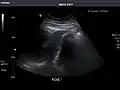

Right kidney -

Kidneys: Right and left kidneys measure 11.5 cm and 12 cm in length respectively. No hydronephrosis. Small left lower pole kidney cyst.